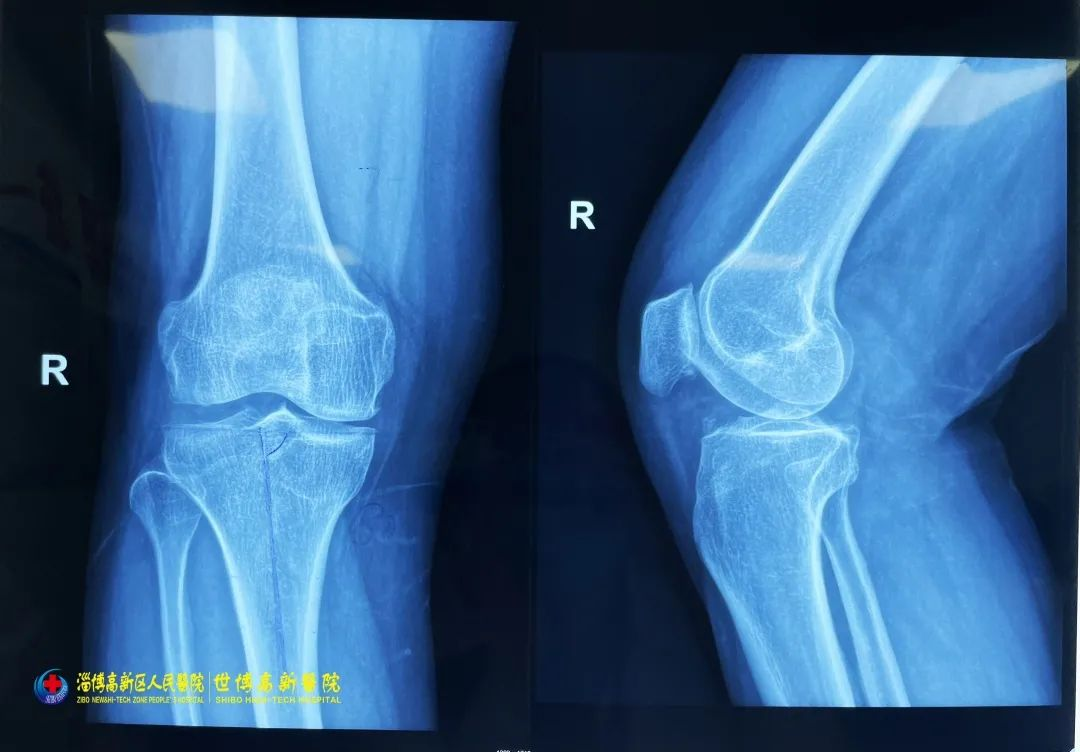

2023-03-06近日,淄博世博高新医院收治了一名膝关节病(右侧)患者,并为其成功进行右膝人工关节表面置换术,手术过程顺利,术后治疗、护理及时、个性、